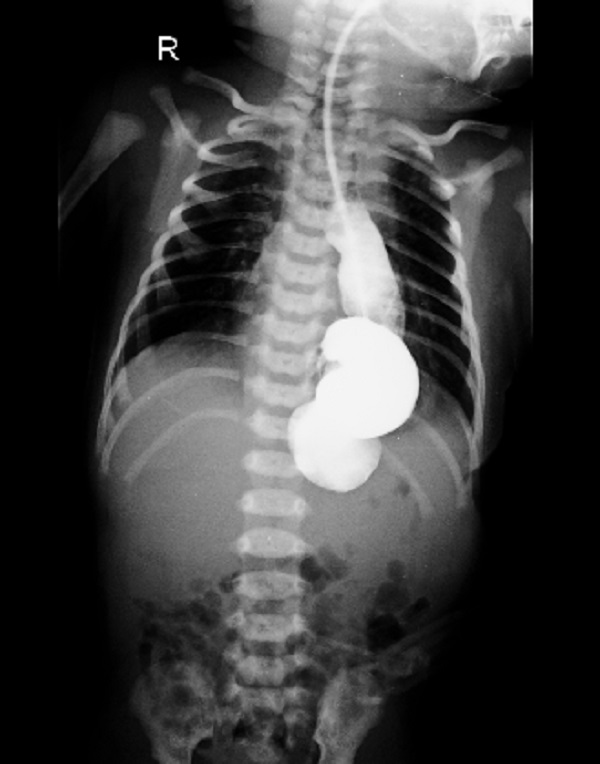

A 5-day-old male term baby (with dysmorphic features) weighing 3.4 kilograms was evaluated for an antenatally diagnosed double aortic arch on fetal echocardiography. A postnatal echocardiogram also suggested the same. CT scan thorax was done which showed a large posterior diaphragmatic hernia on the left side with herniation of the abnormally rotated stomach into the left hemithorax. Mild dilatation of the esophagus in its entire extent was also noted. Great vessels in the thorax were torturous but had normal branching pattern. A double aortic arch was not appreciated. The patient was not tolerating breastfeed, hence further workup was planned. The upper gastrointestinal contrast study showed a part of the stomach in the thorax along with tortuous and dilated esophagus (Fig. 1). At operation, the stomach was completely herniated into the thorax with associated organoaxial volvulus. The stomach was viable, therefore, a reduced back and detwisted Two cm defect was noted at the esophageal hiatus on the left side of the spine, covered by a lax peritoneal sac. The paraesophageal defect was closed. Intraoperatively a small eventration of the left diaphragm was noted which was also plicated during the procedure. Antireflux procedure and gastropexy were not carried out. The baby withstood the procedure well.

Figure 1

Contrast study showing intrathoracic rotated stomach.